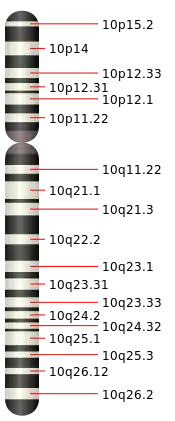

Chromosome 10 humain

Le chromosome 10 est un des 24 chromosomes humains. C'est l'un des 22 autosomes.